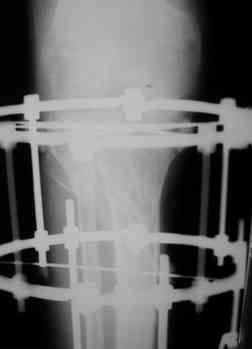

Р-граммы за март и апрель